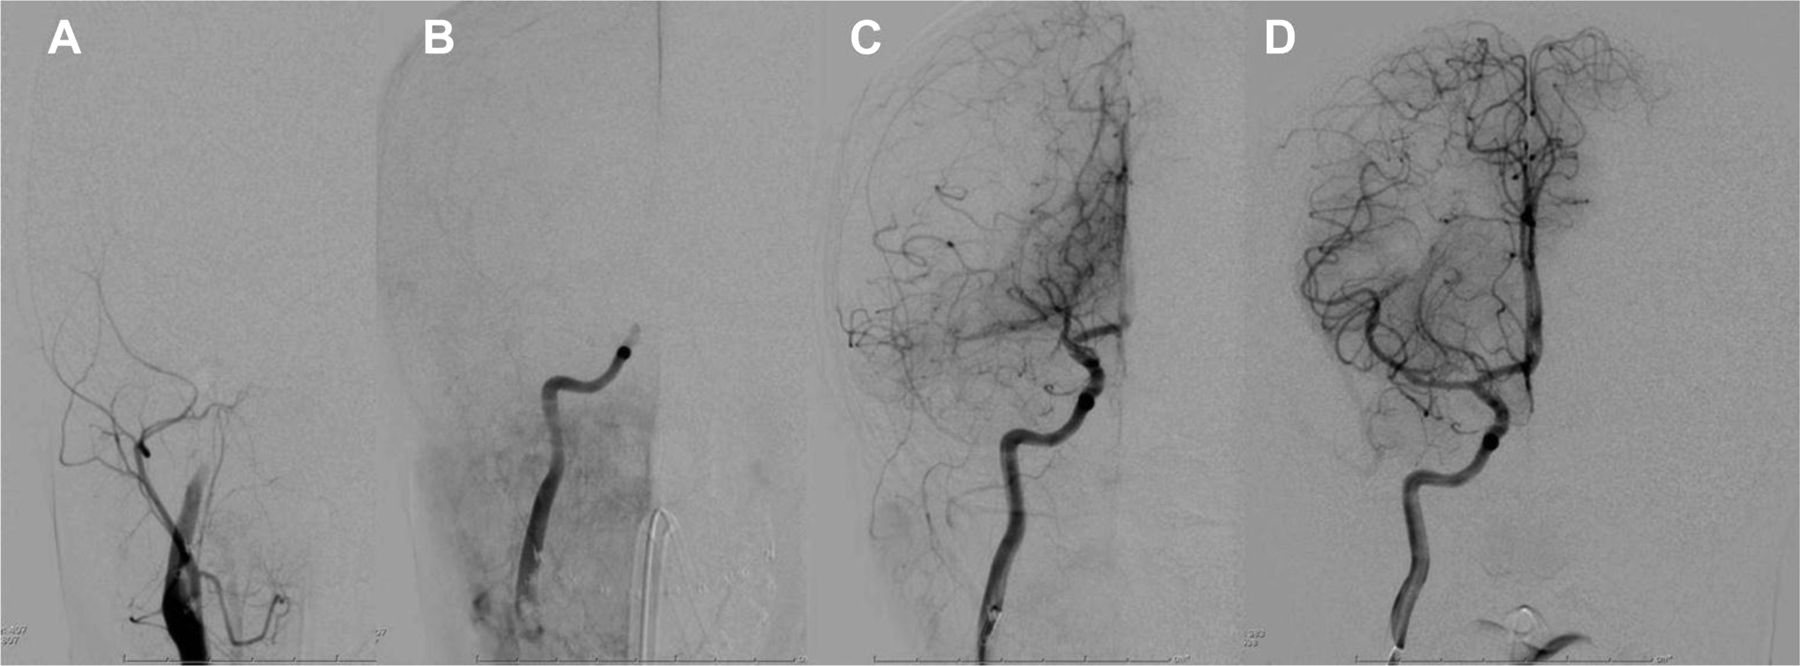

额血管造影的右颈总动脉(a和B,预处理)和对ICA注入(分别C和D,内部和后处理)在历史的一名14岁的男孩心肌病和心律失常出现急性左轻偏瘫。他不是一个候选人与tPA治疗。早期(A)和(B)动脉晚期阶段预处理证明没有流眼动脉之上。威胁人口众多疆域广阔的半球缺血在这样的一个年轻的病人带来了一个巨大的水肿和椎间盘突出的风险。动脉期图像使用后0.041半影吸入microcatheter和分离器的ICA终点站(C)演示了ICA终点站的不透明,沟通后动脉,后大脑枝状大烛台,大脑前动脉近端。动脉期图像使用后的0.032半影系统M1中脑部分演示了ICA终点站的不透明,前大脑枝状大烛台,M1, MCA和上级部门。

审查表的显示,近三分之一的儿童AIS报道病例通过血管内治疗手段,使用机械血栓切除术(11/34例),而在23/34,仅IA溶栓(tPA或尿激酶)管理。34总数的8例并发颅内出血(尽管在7/8无症状)。引人注目的是,机械血栓切除术与只有一个这些8出血事件的情况下,产生的出血率1/11或9.1%,病例治疗机械;此外,在这一情况下,IA tPA是管理。相反,IA溶栓就管理在出血报告病例的7/8,收益率的出血率7/23或30.4%,病例与IA溶栓治疗。因此,我们的方法使用IA tPA小心,尽量单独使用机械方法或其他机械增加使用IA tPA仔细等方法通过导电带,microcatheter血栓注入intrathrombus tPA时连续几次。熟悉的温柔的设置牵引和伟大的儿科护理需要情况下为了避免血管损伤,这种机械装置可能比简单的tPA IA注射更安全。此外,我们保守限制IA tPA剂量为0.2毫克/公斤,最大剂量为12毫克。一个例子使用的半影设备安全机械血栓切除术中显示了一名14岁的男孩图。